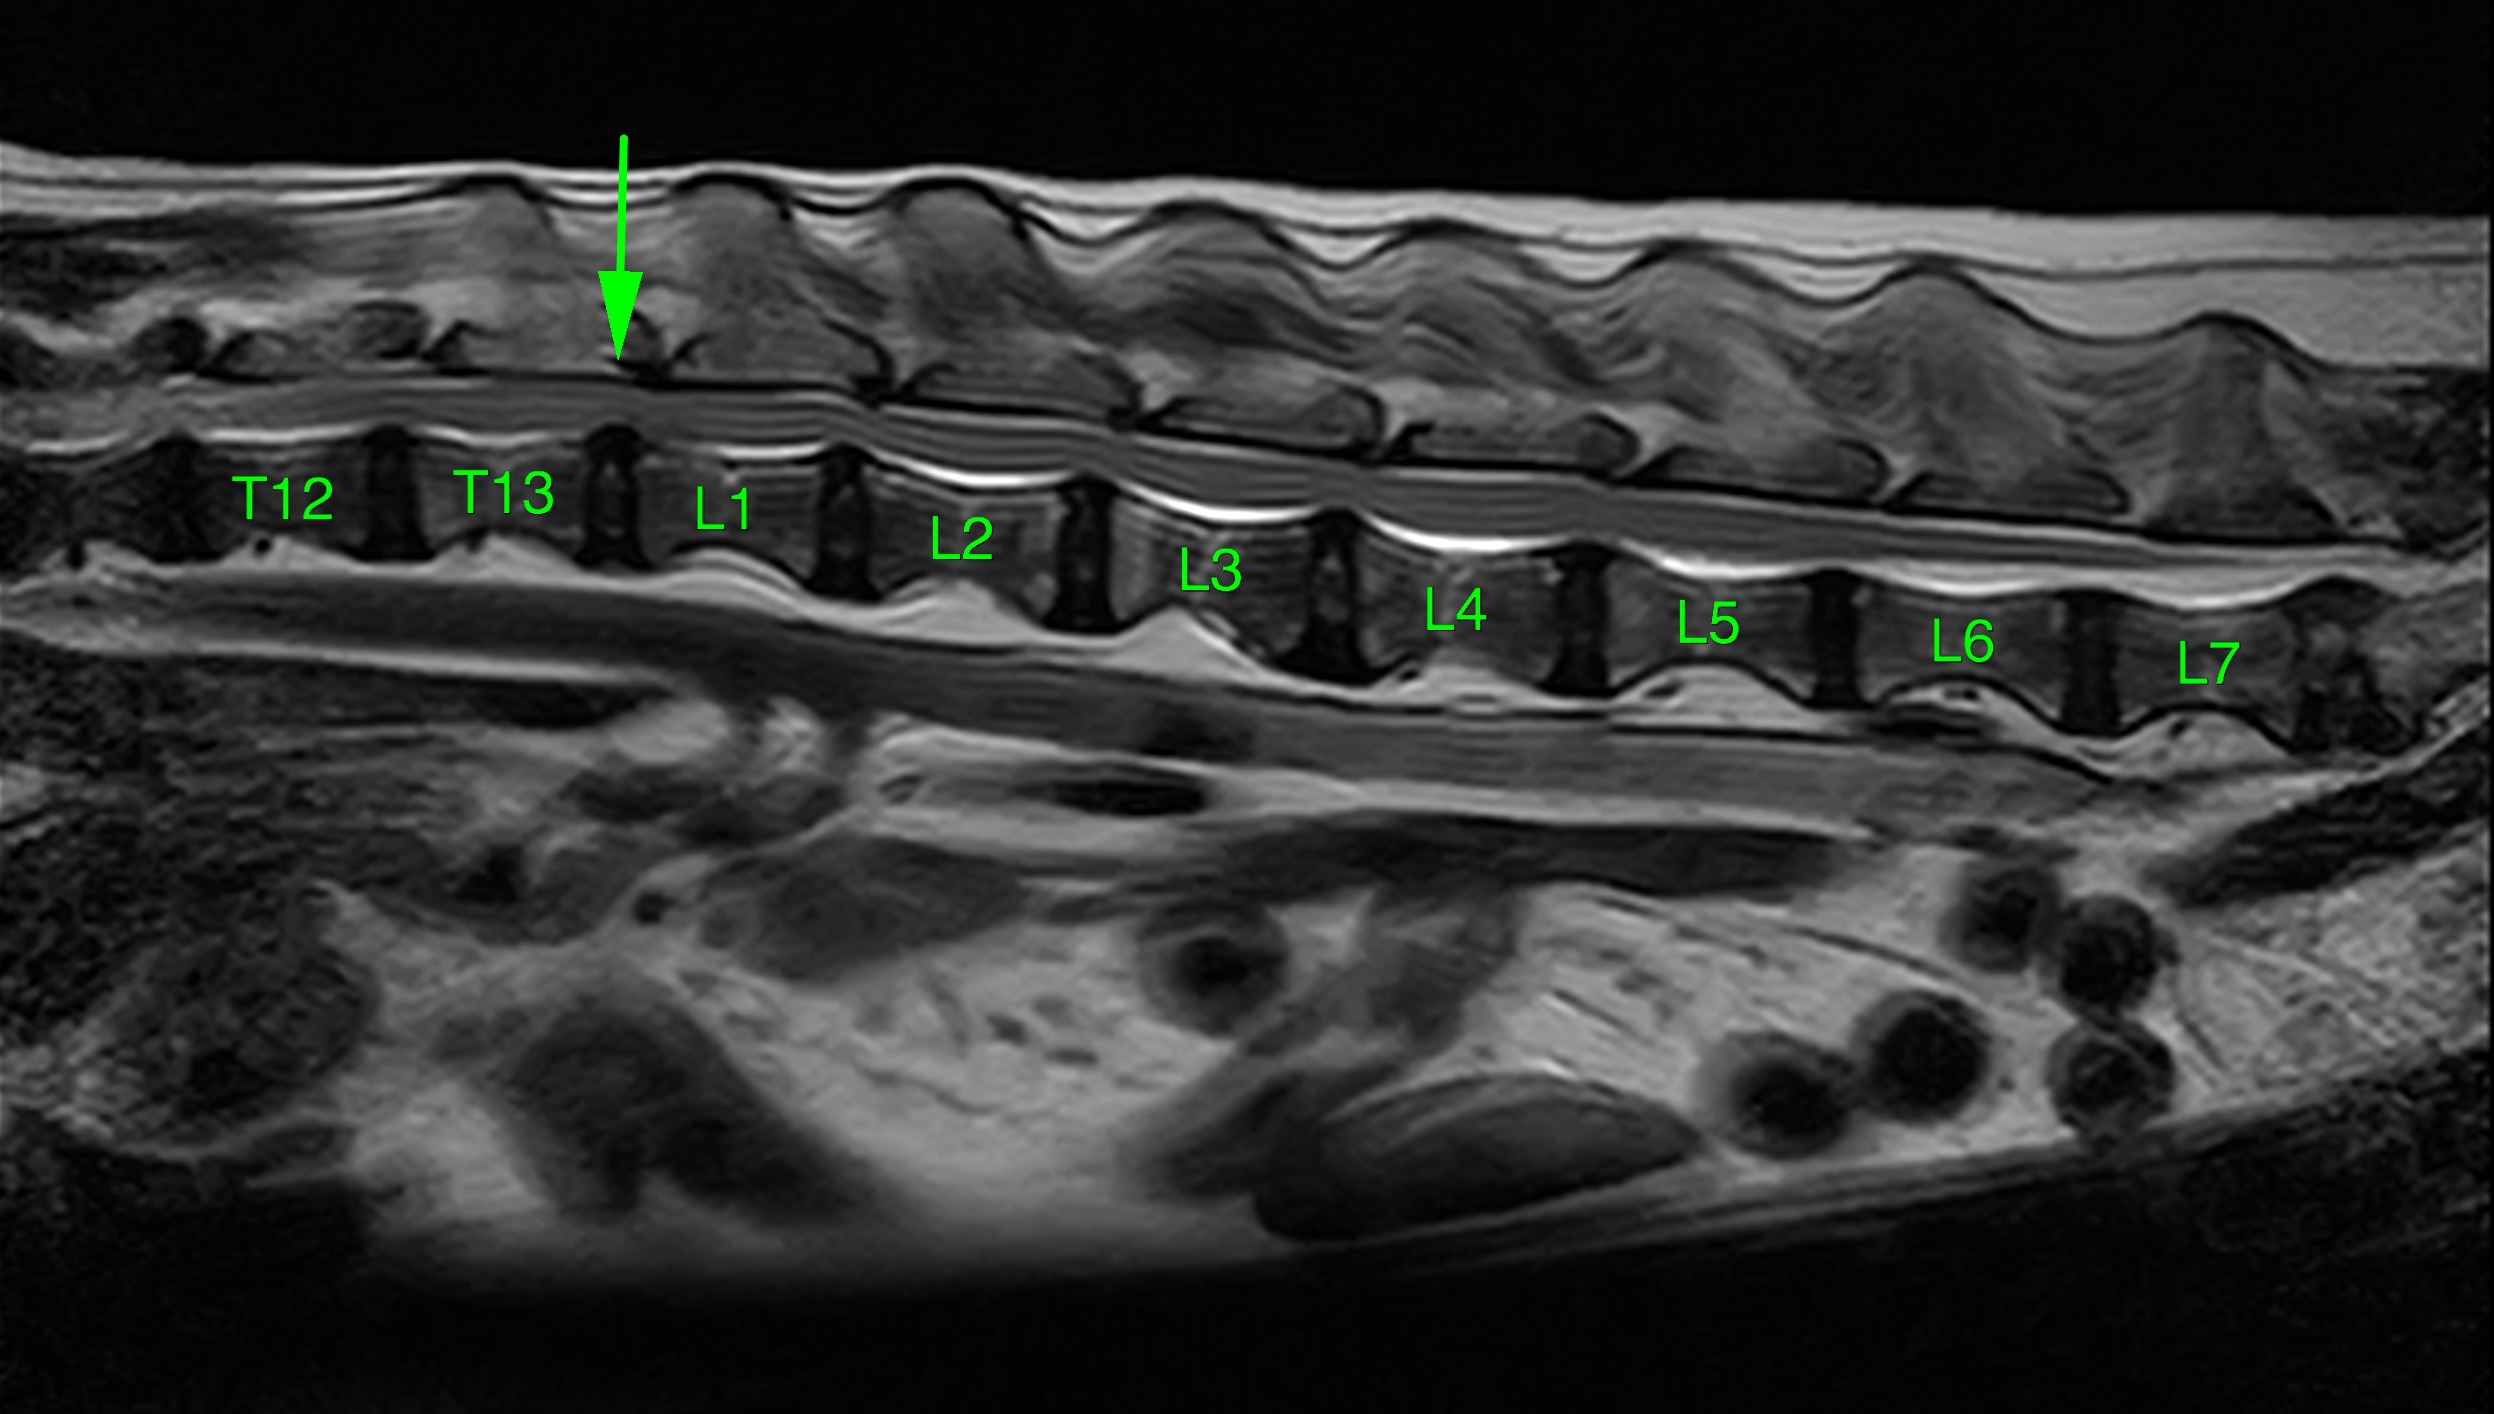

MRI画像(T2-Sagtal像:T13-L1間にて圧迫所見を確認)